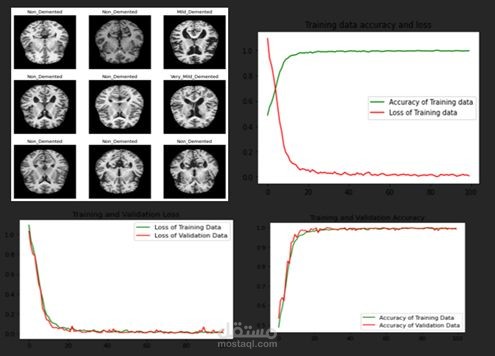

يهدف المشروع إلى تحليل التآثرات الجينية (Epistasis) للكشف عن التفاعلات بين الجينات المرتبطة بمرض ألزهايمر، وذلك باستخدام تقنيات تعلم الآلة وطرق التحليل الإحصائي.

تطبيق خوارزميات تعلم الآلة لاكتشاف العلاقات المخفية بين الجينات.

استخدام تقنيات التعلم الجماعي (Ensemble Learning) لتحسين دقة النتائج.

عرض النتائج من خلال تقارير ورسوم بيانية توضح أهم التفاعلات الجينية المكتشفة.

هدف المشروع هو المساهمة في فهم الأسس الجينية لمرض ألزهايمر، مما يساعد الباحثين والأطباء في تطوير استراتيجيات أفضل للتشخيص المبكر والعلاج المستقبلي.